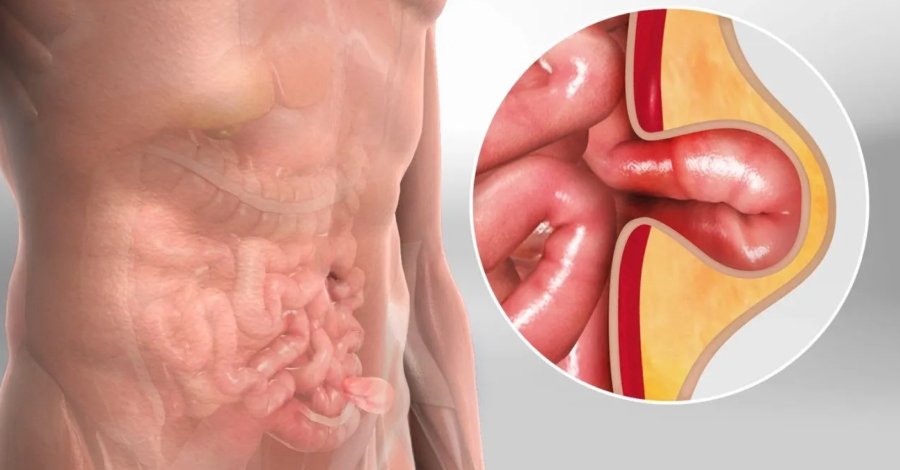

Inguinal y femoral

• Inguinal y femoral